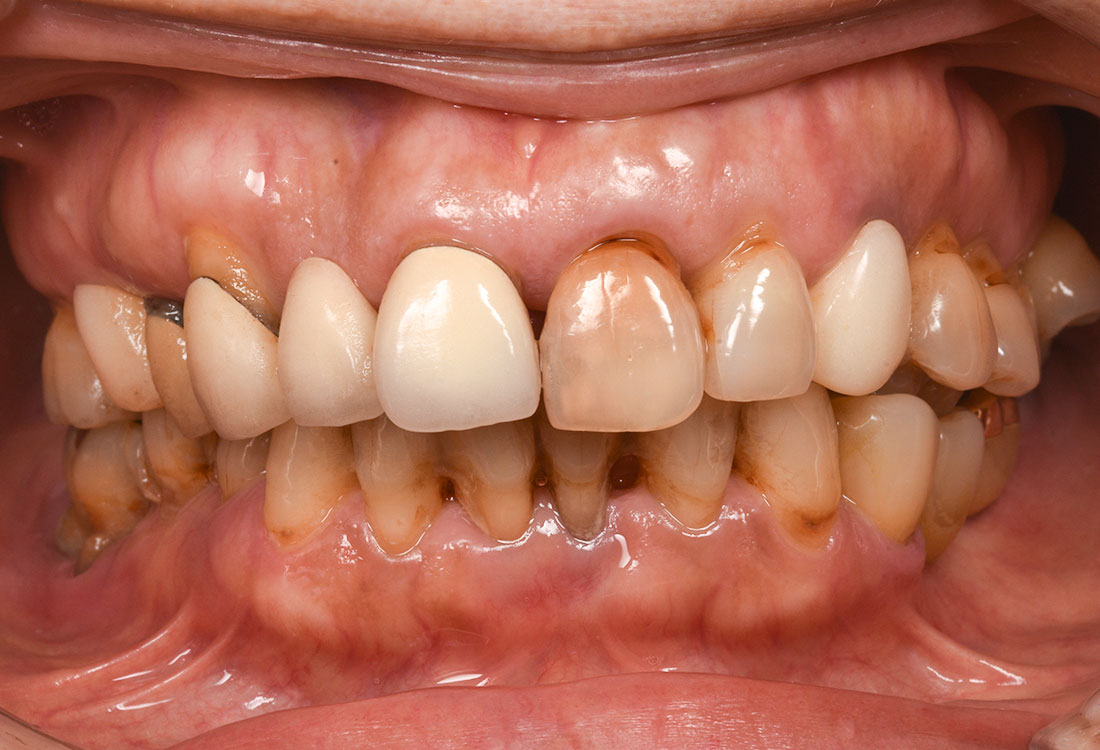

治療症例 Case1

Treatment cases

ご相談内容

- 歯並びが気になる

- 矯正をする時間が取れないので被せ物で治していきたい

治療前

治療後

今回は前歯をグラデーションカラーのジルコニア、奥歯をセレックで治療しました。

見た目の美しさのポイントになるスマイルラインも整っています。